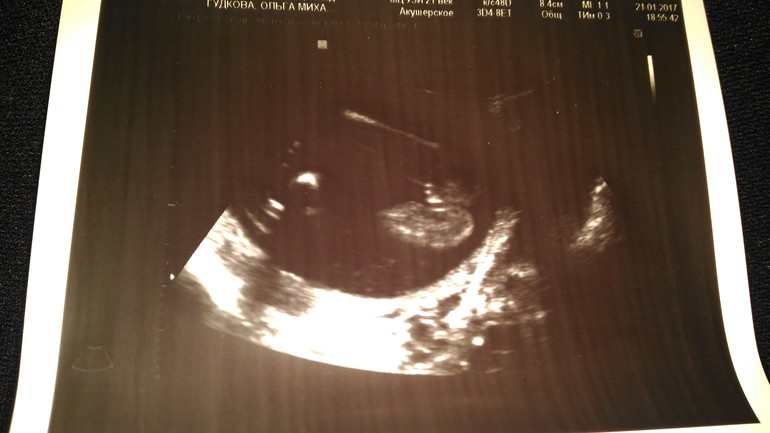

Ольга Михайлова в Здоровье будущей мамы 9 лет Привет девушки! Как думаете, какой пол? 18 недель Результаты: УЗИ, КТГ, доплера, скрининга Посмотрите еще 20 записей на эту тему Отменить Ответить Ольга Михайлова Спасибо за ответы) узист сказала, скорей всего девочка 23.01.2017 Ответить Матильда Похожа на девочку,а узистка что сказала? вот мальчик 👦 23.01.2017 Ответить Юлия Ч Похоже на девочку. 23.01.2017 Ответить Дарья Мне кажется мальчик! 22.01.2017 Ответить Anastasia Как по мне, так больше на девочку похоже.. вот в сравнении (справа мальчик). 22.01.2017 Ответить Евгения 50 на 50) 22.01.2017 Ответить Виктория по мне так мальчик 22.01.2017 Ответить Доплер - нууууу я прям растерялась... короткая шейка на 21 неделе. Чаты Беременных Выберите чат: Январята-2026 Февралята-2026 Мартята-2026 Апрелята-2026 Майчата-2026 Июнята-2026 Июлята-2026 Августята-2026